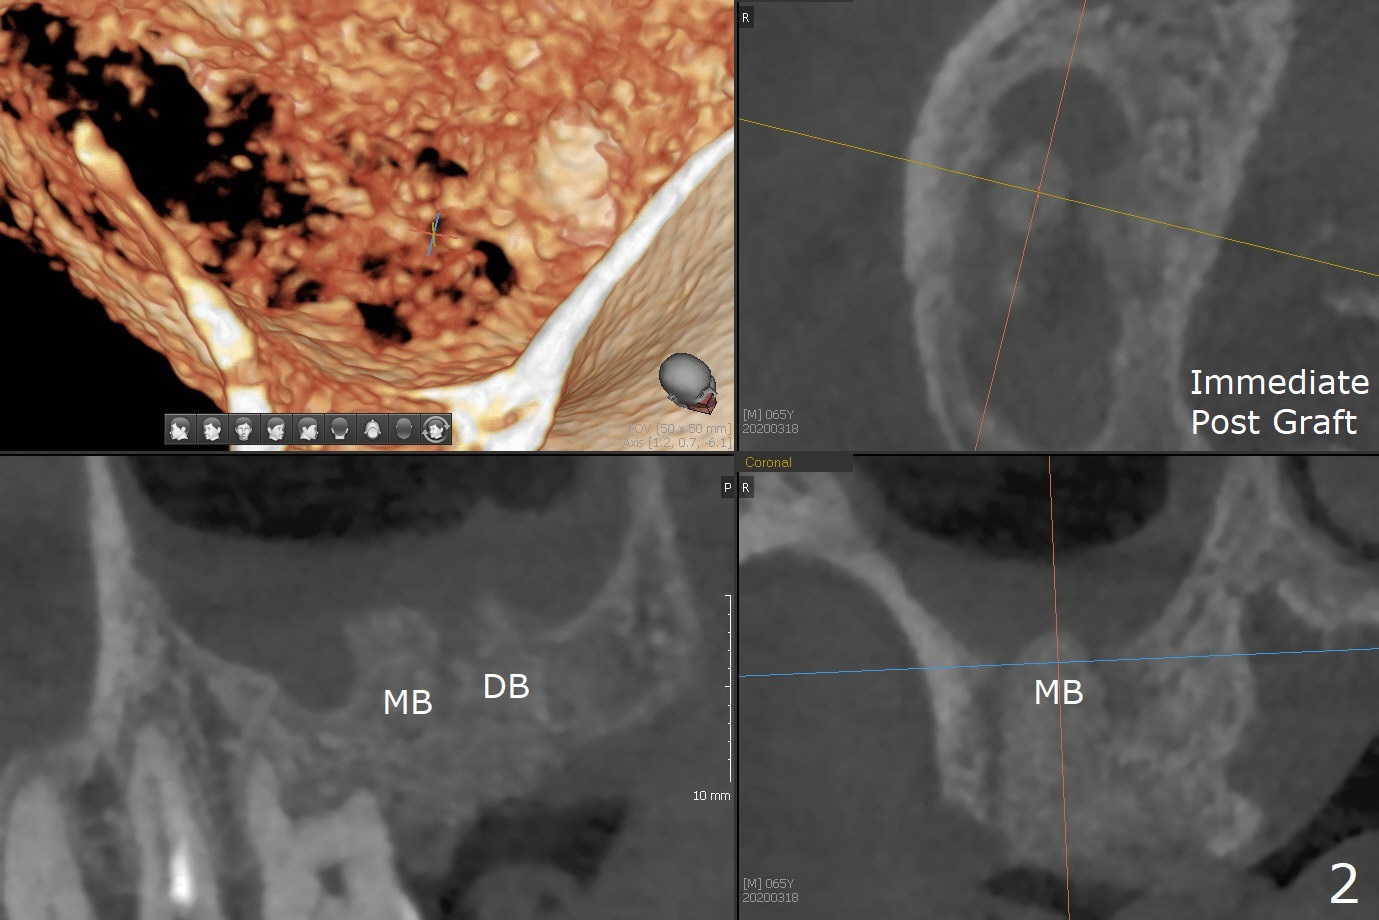

The apices of the mesio-buccal (MB) and disto-buccal (DB) roots are soft when the tooth #2 is extracted. After socket debridement, there is no air leak. Minera-lized cortical and cancellous mix (50/50) hydrated with ~ .25 ml of .3 mg/ml of rhPDGF-BB is placed in MB and DB sockets and pushed upward with a curette. Finally the whole socket is filled up to the crest and a piece of 8x8 mm BioXclude is placed and sutured in placed with 4-0 PGA (Fig.1-3). In fact sinus lift is accomplished moderately MB and DB (Fig.2,3). In fact the density of the bone graft 6 months postop remains the same as immediate postop, similar to the native bone as well (Fig.4,5). With socket preservation, a longer implant will be placed at #2 (Fig.6, as compared 8.5 mm at #15 without bone graft).